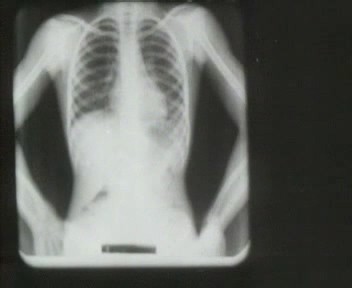

In 1947 blijkt tijdens een onderzoek dat bijna de helft van de schooljeugd in Boekel ooit besmet is geweest met de bacterie die tuberculose kan veroorzaken. Daarom gingen de gemeente en volksgezondheidsinspectie over tot een grootschalige screening: alle inwoners van Boekel krijgen in 1948 de oproep om deel te nemen aan een röntgenologisch borstonderzoek.

Alle inwoners van Boekel krijgen in 1948 dus de oproep om deel te nemen aan het onderzoek. Bijna 96% van de bevolking doet mee en van elk van hen worden de longen nagekeken door middel van een röntgenfoto.

Voor het eerst in de geschiedenis van de tuberculosebestrijding in ons land werd er een momentopname gemaakt van de verspreiding van tbc binnen één plaats. De resultaten vielen alleszins mee, uiteindelijk bleken maar 20 mensen lichte tbc te hebben (die behandeld kon worden).